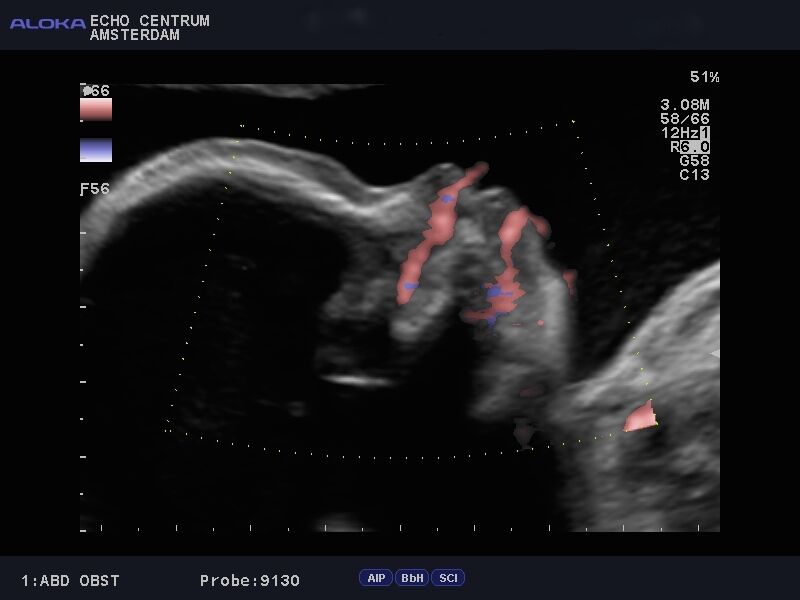

Onlangs had ik een hele leuke ervaring. Ik ben een gepensioneerd gynaecoloog, en was vroeger zeer begaan met mijn verloskundige patiënten. Mijn schoondochter en zoon nodigden mij uit om mee te gaan naar een "pretecho"van dr. Papa in Amsterdam. Wij, gynaecologen, hebben geweldige vooroordelen tegen een zogenaamde pret echo en vinden ze vaak overbodig. Nou dit pakte anders uit. We werden verwelkomd door een bijzonder charmante, leuke en vlot bespraakte Nederlandse Antiliaan: Elvin Papa, arts echoscopist. Daar zat hij in zijn spreekkamer, in een prachtig pand, achter een prachtig echo apparaat, dat voor mijn toenmalige ziekenhuis te duur was om voor ons gynaecologen aan te schaffen!! Alles werd getoond, het hele lichaampje van de baby. Alle organen, het geslacht, hart en bloedvaten noem maar op. Prettig was dat je in 3D een hele goede indruk krijgt van het gezichtje. Het hele onderzoek verliep voorspoedig en was heel relaxed. Papa doet veel aan nascholing en houdt de ontwikkelingen op echo gebied heel goed bij. Echo onderzoek kan heel vervelende zaken aan het licht brengen. Wij hadden een goed nieuws echo, dus dat is feest en lol. Belangrijk lijkt mij wel dat je met een slechte echo bij Elvin Papa in goede handen bent. Hij zal weten hoe je te troosten en hoe je door te verwijzen. Hopelijk hoeft dat niet vaak. Ik wens hem nog veel succes toe.

Bij deze willen wij je nog even bedanken voor de mooie en bijzondere echo die je van onze tweeling hebt gemaakt (de echo lukte zo goed!). Aangezien we ons nogal veel zorgen maakten was de echo precies de positieve input die we nodig hadden. We zijn natuurlijk een beetje beroepsgedeformeerd en wij vonden het schitterend dat je met de moderne technieken (je superecho-apparaat!!) de anatomie van die piepkleine mensjes zo goed kunt zien! Nogmaals ontzettend bedankt.

Al jaren hoorde ik vele goede verhalen van cliënten en collega's. Toen ik zelf zwanger was, wilde ik dan ook graag eens een echo bij drs. Papa mee maken. En ik begreep meteen waarom iedereen altijd zo enthousiast was! Via de (2,3 & 4D) echo van Elvin Papa maakten wij voor het eerst kennis met ons kindje. Dit was toch weer heel anders dan de standaard medische echo's die hieraan vooraf waren gegaan. Ik was ontroerd! Sinds deze echo voelde ik meer 'band' met ons ongeboren kindje. Wij zagen op de echo dat hij voortdurend zijn handjes voor zijn gezicht hield en Elvin voorspelde dat wij dit vast terug zouden zien als hij eenmaal in de wieg lag. En ja hoor, nu onze zoon er is herkenden wij onmiddellijk zowel het gezichtje, als de handjes voor het gezicht waar hij erg aan verknocht lijkt. Zo mooi! Verder vonden wij het heel prettig dat zo'n deskundig en vriendelijk persoon als Elvin alle items van de 20 weken-echo nog eens bekeek en in begrijpelijke taal aan mijn man, (schoon)moeders en mij toelichtte. Ik kan het al mijn cliënten aanraden!